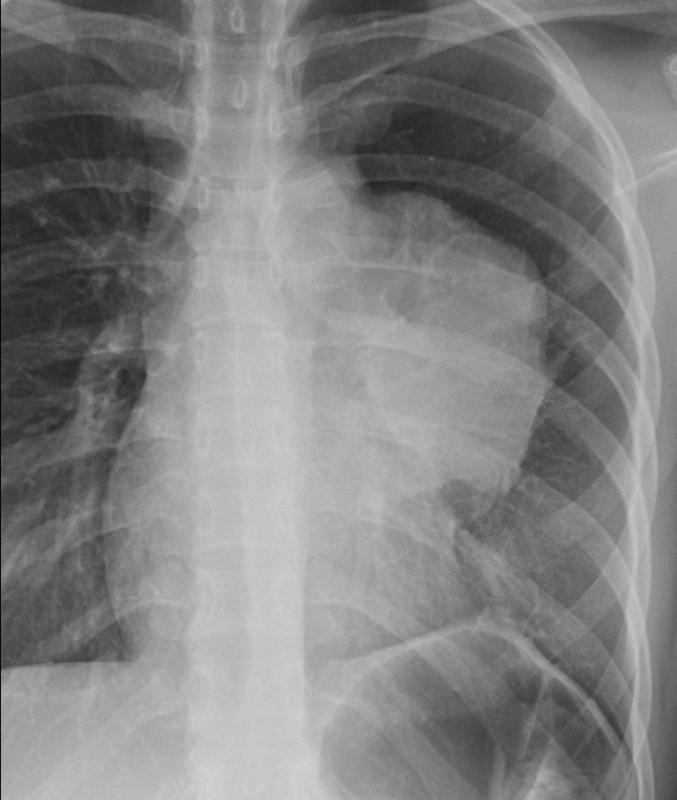

Thymic carcinoma PA